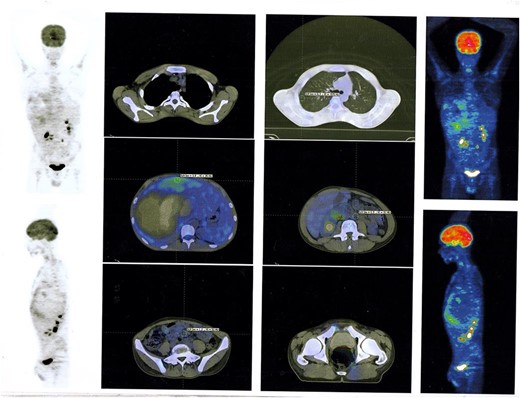

The overall treatment time that includes surgical treatment and chemotherapy was nearly 11 months. After following up with the patient for one year, PET Scan Multi Slice showed normal findings without signs of local recurrence, without nodal or visceral metabolic activity (Fig. 5). Regular clinic visits and periodic check-up every 6 months for 3 years showed the patient in good health without signs of recurrence.

PET Scan Multi Slice showed normal findings without signs of local recurrence, without nodal or visceral metabolic activity.